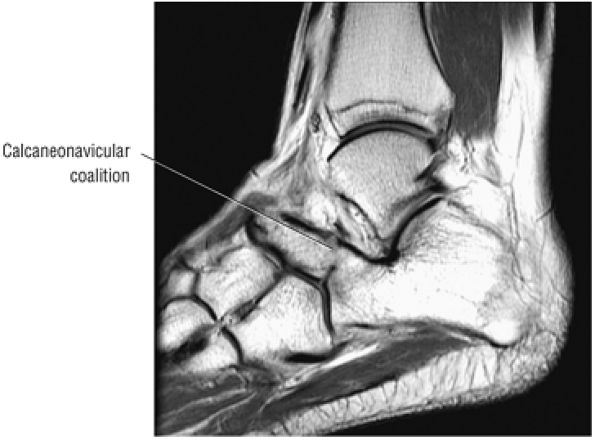

The spring ligament complex consists of three components: the lateral, intermediate, and superomedial oblique calcaneonavicular ligaments.

-

structures are critical static stabilizers of the medial longitudinal arch of the foot, providing support for the head of the talus at the talocalcaneonavicular joint (or acetabulum pedis). The other major stabilizer of the medial longitudinal arch, the PTT, is a dynamic stabilizer. Pathology of the spring ligament complex rarely occurs in isolation and is almost always associated with PTT dysfunction. Attention to the components of the spring ligament on routine MR imaging of the foot is important, since there is often a cascade of failures that can lead to or be seen with acquired pes planus deformity.